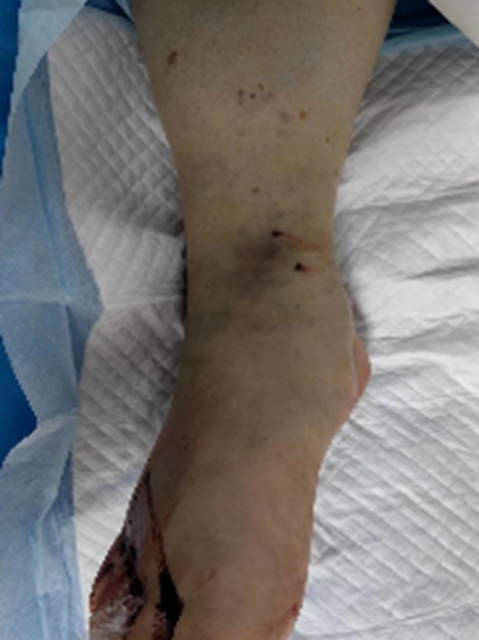

伤后仅仅6个小时,刘大叔便感觉到左下肢的肿胀和疼痛在不断加剧,而且肿胀范围从左踝迅速蔓延至左膝关节处。此时,他意识到问题的严重性。在当地医院就诊时,医生通过辨认毒蛇照片,确定咬伤刘大叔的是原矛头蝮蛇,随即展开一系列治疗。但刘大叔的病情却并未如预期般好转,反而愈发严重。肢体肿胀、疼痛持续蔓延,直至大腿腹股沟处,肌红蛋白不断升高,出现肾功异常、无尿、心衰等一系列危急情况。随即,刘大叔被转至西南医科大学附属中医医院急诊科做进一步的治疗。

经过两天的紧张治疗,刘大叔的病情终于出现了一丝转机,肾功能有所好转,心衰症状也得到了一定程度的缓解。然而一波未平,一波又起,刘大叔出现了新的临床症状——发热,而且小腿依然肿胀明显,皮温居高不下。难道是小腿坏死伴感染加重了?医生们不敢有丝毫懈怠,根据 MRI 检查情况,他们发现刘大叔的左小腿、左脚存在组织坏死的情况,果断决定进行手术切开减压引流,清除病灶坏死组织。手术中,医生们看到左小腿下段内侧伤口深层筋膜部分坏死,比目鱼肌少许肌肉变黑坏死。